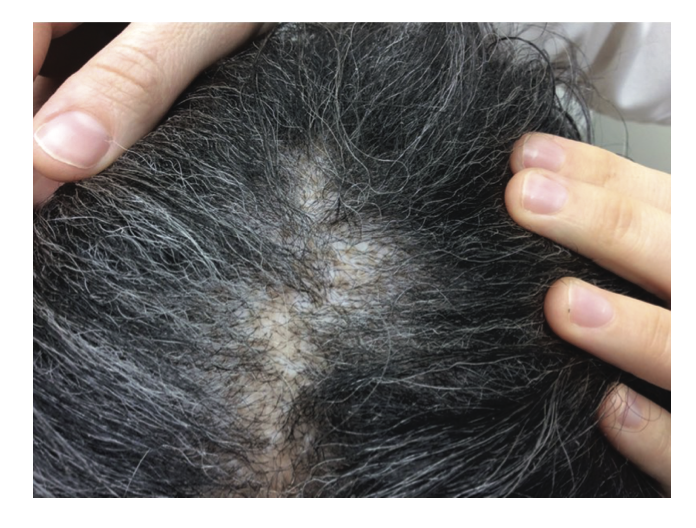

Scalp Sarcoidosis. Scalp sarcoidosis is a great imitator. Note the orange or “apple jelly” color in a female with scalp involvement. Image from Long T et al. Severe scalp sarcoidosis in an unlikely patient. JAAD Case Rep . 2020 Apr 24;6(11):1165-1166. Image used here with creative commons license.

Clinically, the lesions often have an orange color. They do not always especially in darker skin types. It’s important to realize that scalp sarcoidosis truly is one of the great imitators and can take on many many different appearances! and may look very similar to lichen planopilaris, discoid lupus, pseudopelade, central centrifugal cicatricial alopecia, acne keloidalis, folliculitis decalvans, necrobiosis lipoidica, scleroderma or even alopecia areata at first glance. Some present like diffuse scaling and some present with ulcerations. Just like the skin lesions (which we’ll review below), scalp sarcoidosis can take on many forms!